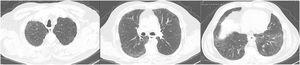

On the 5th day of the second therapeutic cycle (C2D5), patient complained of sudden dyspnea, fever (38.1°C) and presented with rapidly progressive hypoxemia (highest necessary FiO2 was 0.60). The chest X-Ray performed showed bilateral parenchymal infiltrates and blood analyses revealed a moderate increase of inflammatory parameters. Patient was admitted at the Hematology Department. A sepsis screen was carried out, empiric antibiotics prescribed, and an angio-thoracic CT was performed to exclude pulmonary thromboembolism (PE). The scan did not show PE but revealed diffuse parenchymal ground-glass densification with an “NSIP-like” pattern (Fig. 1).

A pulmonology evaluation was requested. Suspected toxicity to azacytidine was suggested, once patient had a Naranjo score of 7 (probable ADR), and the drug was suspended. A complementary study was carried out. Bronchoalveolar lavage (BAL) showed 320,000 cels/mL, 93% lymphocytosis and an extensive negative microbiological study, namely for Pneumocystis jirovecii and CMV, considering the high risk for opportunistic pulmonary infections in the haemato-oncological setting. Respiratory function tests revealed slight restriction (TLC 74%) and severe decrease in single-breath carbon monoxide diffusing capacity of the lungs (DLCOSB 35% and KCO 61%). Despite the absence of elusive clinical features (no orthopnea, paroxysmal nocturnal dyspnea, crackles or peripheral oedema) and the NT-proBNP and HRCT pattern not suggesting cardiogenic pulmonary oedema, a heart evaluation is generally valuable and, therefore, an initial EKG and a subsequent echocardiogram were conducted and were both normal. The patient was prescribed 3 pulses of methylprednisolone 500 mg, followed by prednisolone 0.75 mg/kg in a slow tapering scheme, under PCP prophylaxis with trimethoprim/sulfamethoxazole. After 10 days there was clinical, gasometrical, and radiological improvement, having been discharged with ambulatory oxygen. After 3 weeks of treatment, a reassessment HRCT revealed a clear improvement, showing bilateral reduction of the ground-glass opacities (Fig. 2), and the 6MWT performed allowed the suspension of the previously prescribed oxygen.